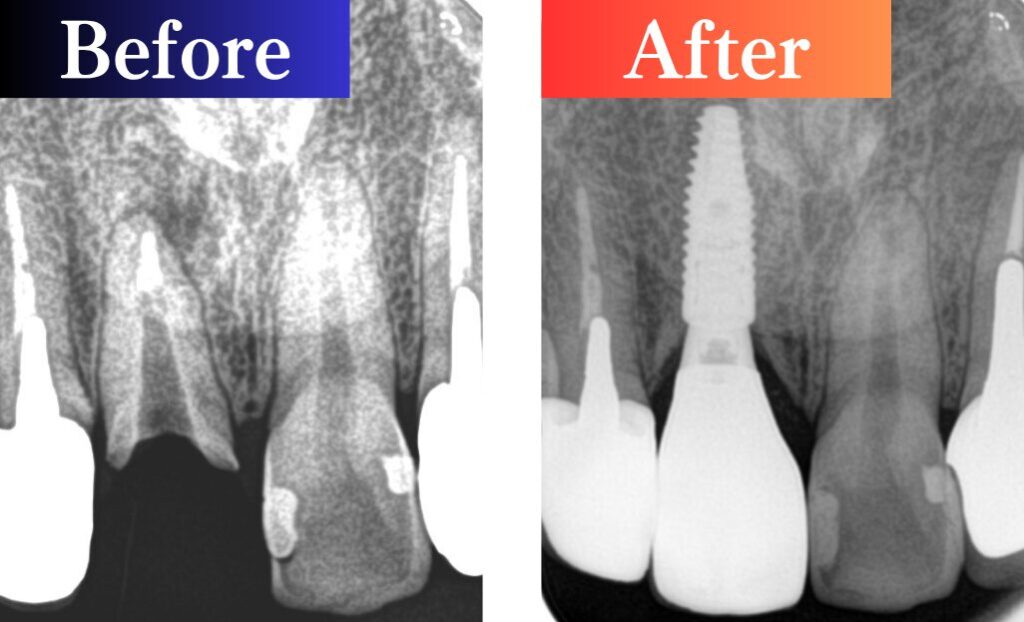

前歯部インプラント・セラミック治療  40代男性

右上の中切歯の根の先に膿がたまり骨が溶けている状態が見られ、歯の根が割れており、保存は難しい状態でした。

骨の吸収が大きかったため、抜歯と同時ではなく、骨の回復を待ってからインプラントを埋入。

その後、仮歯で形やバランスを確認し、自然な見た目に整えました。上部構造(被せ物)はスクリュー固定式(ねじ止め式)を採用。トラブル時にも取り外しができる安心な設計です。

前歯の見た目と機能をしっかり回復し、自然で調和のとれた仕上がりとなりました。